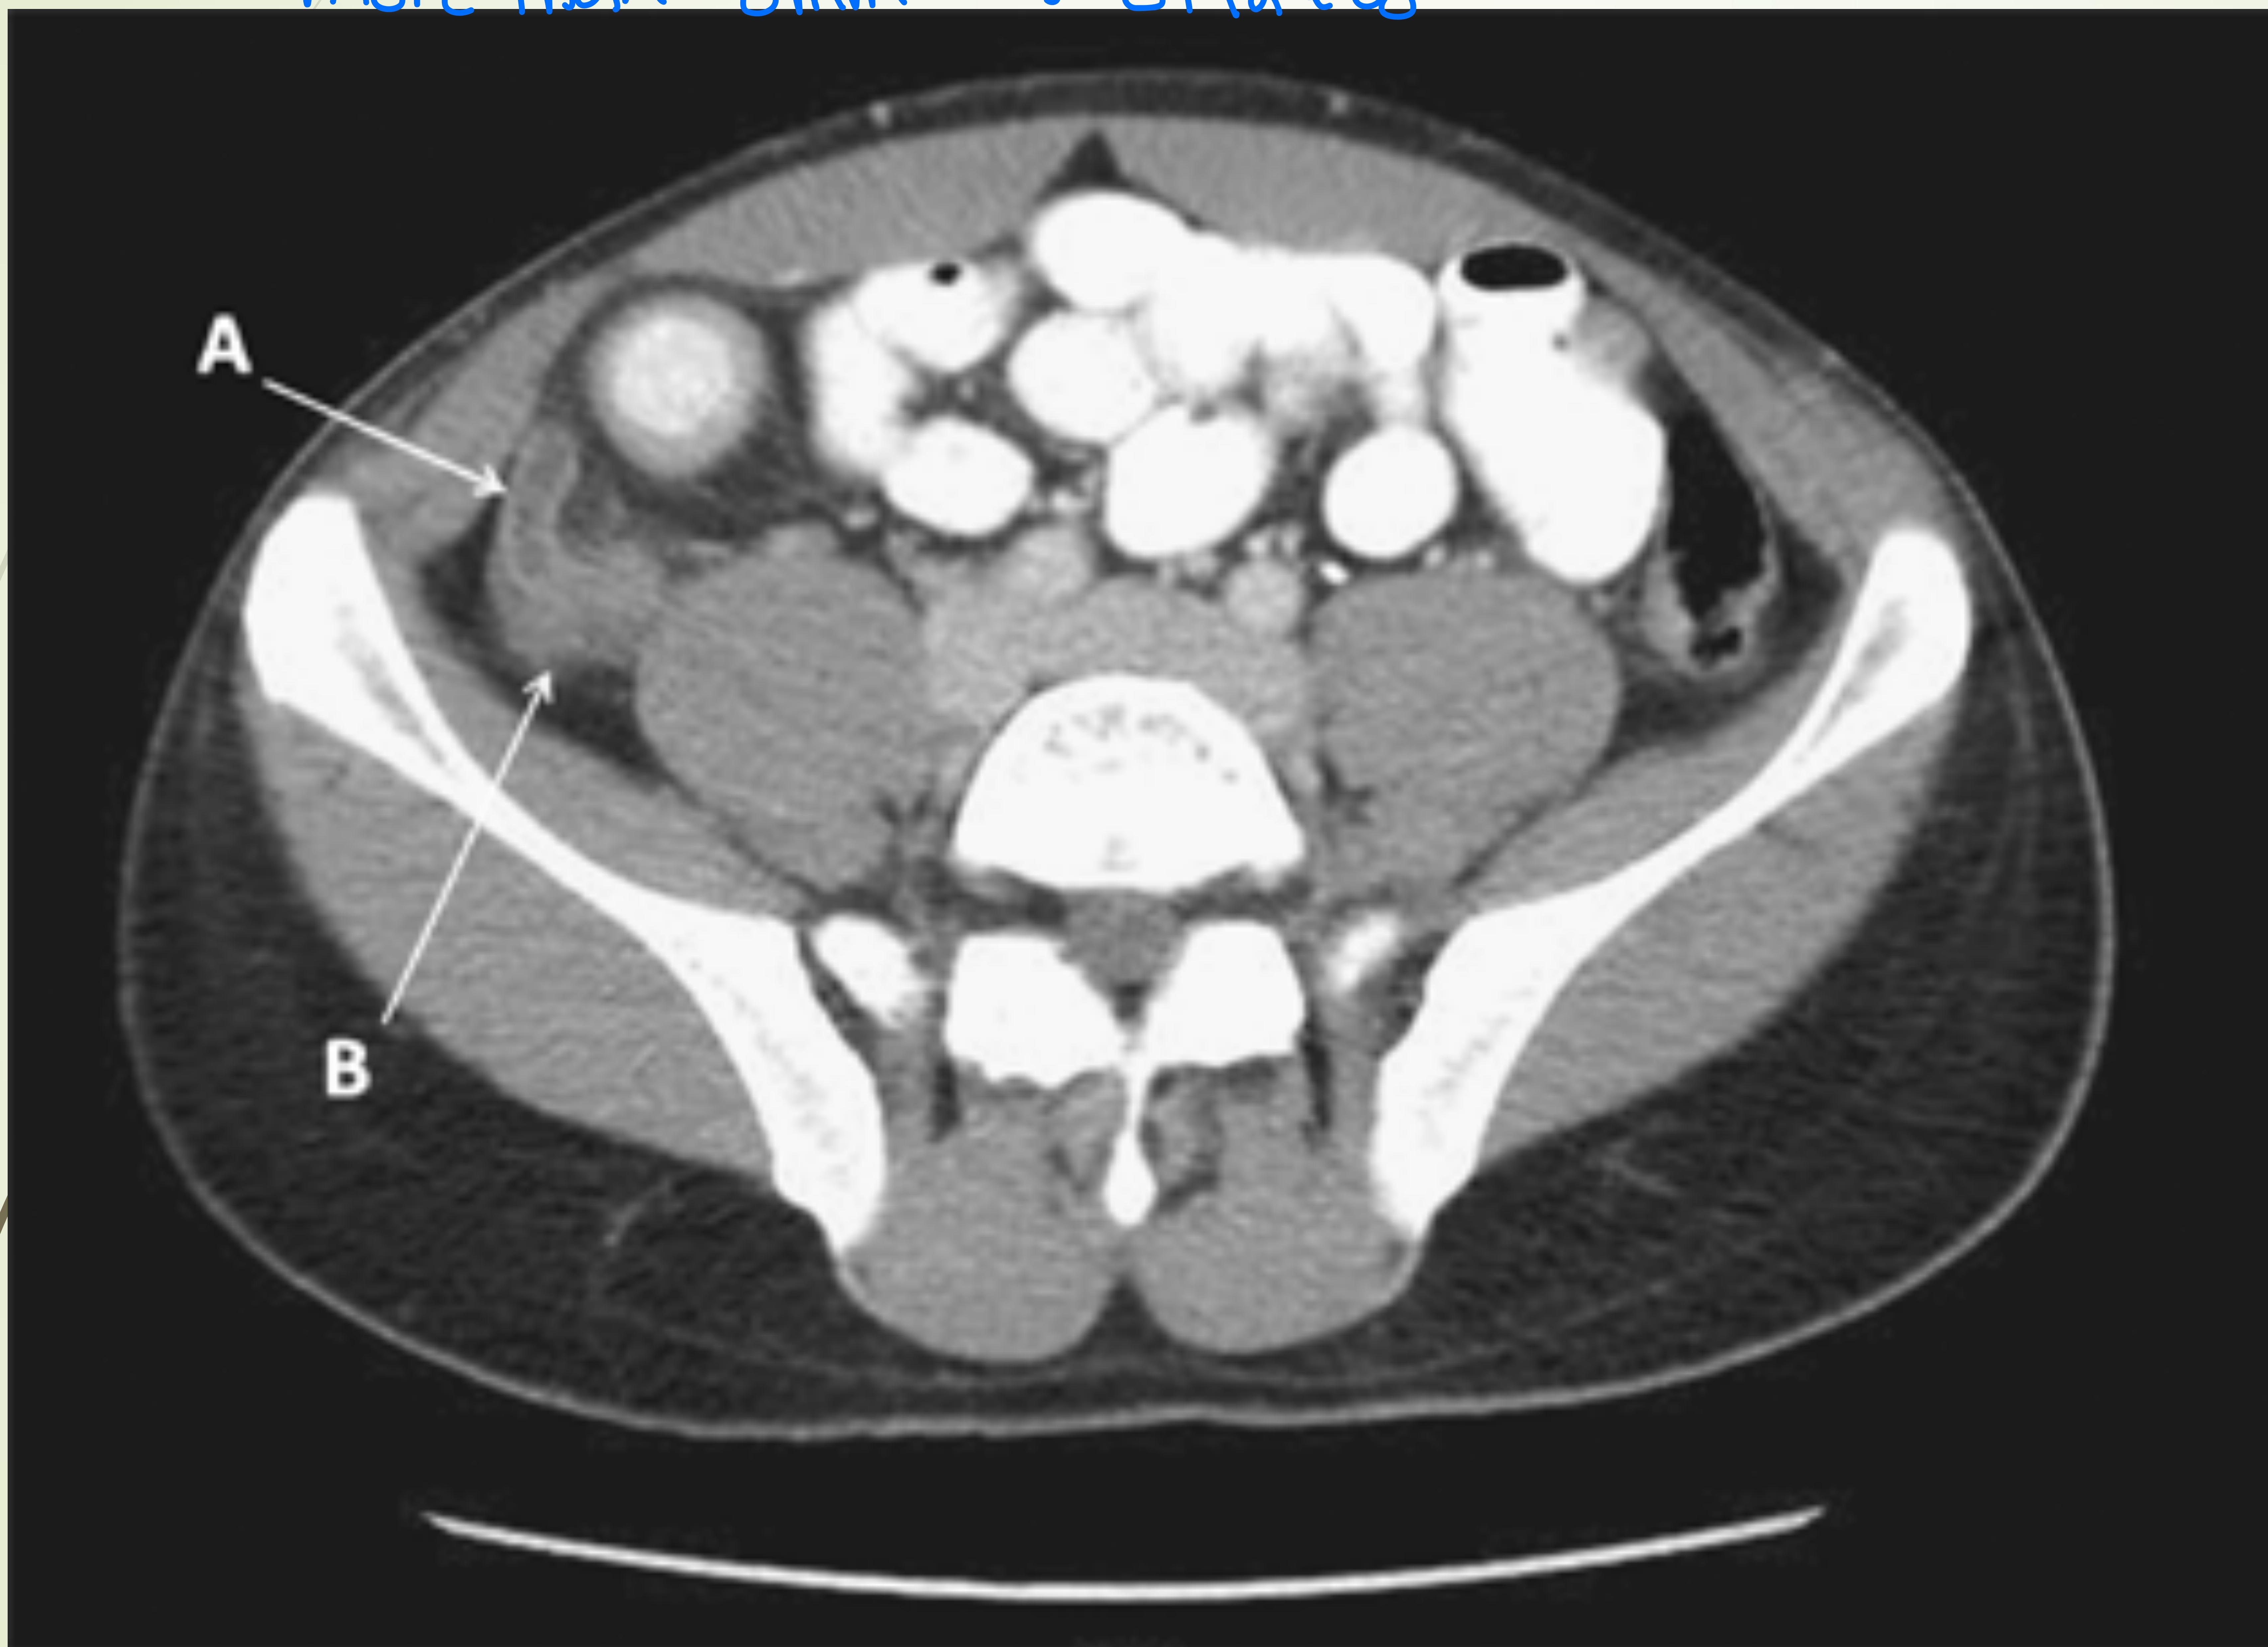

Axial CT scan showing dilated and thickened appendix.

- Diagnosis: CT Scan with contrast in male or nonpreganant women (Gold Standard) showing dilated appendix (>6mm), fat stranding. - otherwise use ultrasound

- CT scan (gold standard) — typical findings:

- Pericecal inflammation

- Abscess or localized fluid collection

- Localized fat stranding